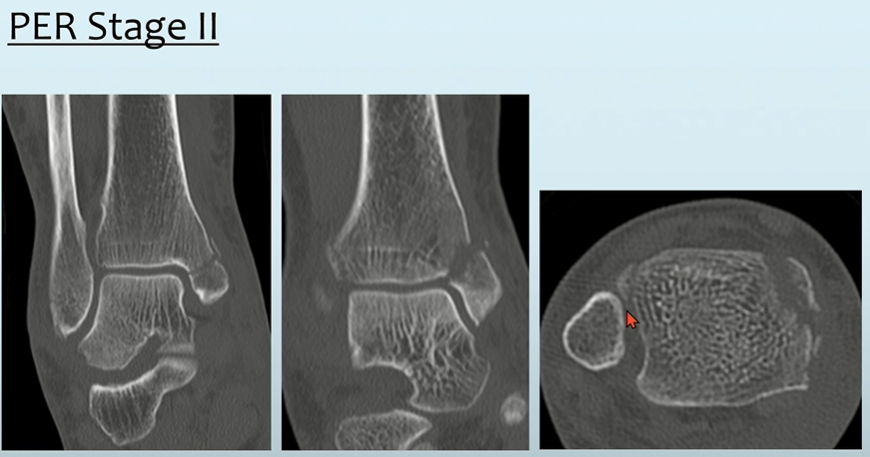

- Stage2: ATFL 손상

- Stage3: high fibular fracture (굉장히 특징적입니다. 높이는 Danis-Weber classification상 C)

실제 영상보면, high fibular fracture가 특징적입니다.